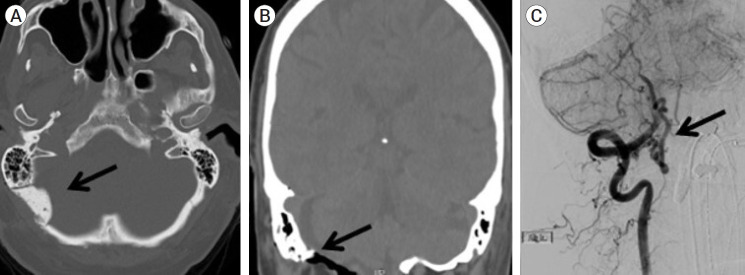

摘要椎动脉硬膜动静脉瘘是一种罕见的疾病。我们报告了一位有晕厥前症状的患者,发现在脑膜后动脉和流入乙状窦的皮质静脉之间有VADAVF。患者最初接受了手术干预,但未能消除分流。使用分流器的血管内治疗提供了明确的分流断开。

Vertebral artery dural arteriovenous fistulae (VADAVF) are a rare entity. We present a patient who experienced pre-syncopal symptoms and was found to have a VADAVF between the posterior meningeal artery and a cortical vein draining into the sigmoid sinus. The patient initially underwent surgical intervention, which failed to obliterate the shunt. Endovascular treatment with use of a flow diverter provided definitive disconnection of the shunt.